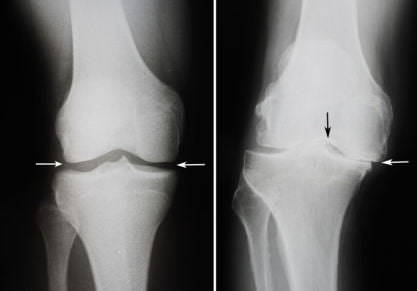

Нарушение деятельности суставов может привести не просто к плохой подвижности, но к полной инвалидности. Естественно, чтобы не допустить такой ситуации, необходимо лечиться. Причем терапия может осуществляться совершенно разными методами. Главное, чтобы она была комбинированной и комплексной. Только в этом случае подвижность можно будет восстановить, а прогрессирование патологии приостановить или существенно замедлить.